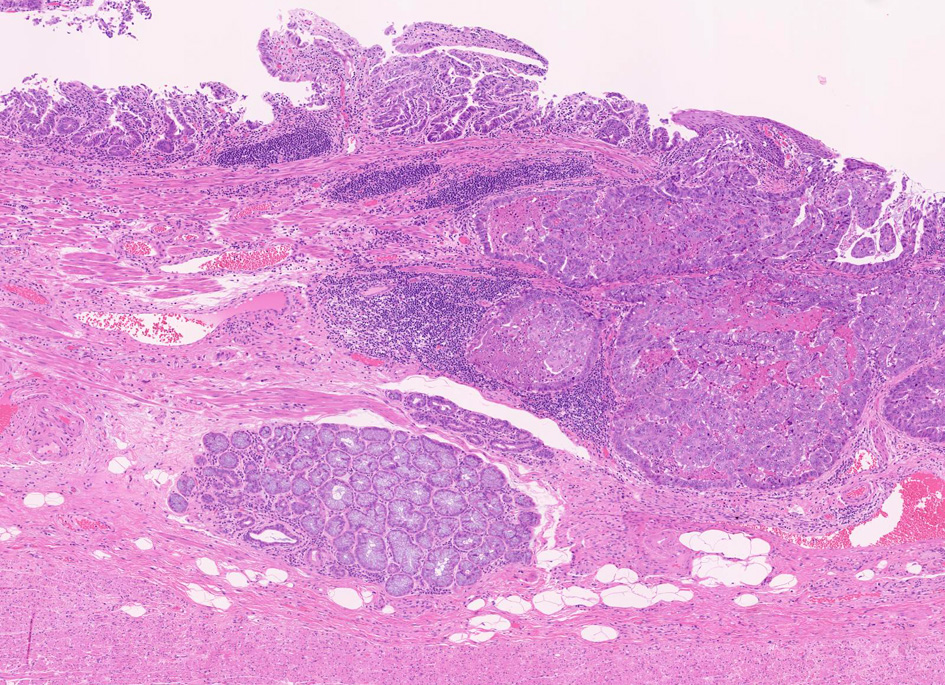

1. 固有食道腺と導管が円柱上皮部位に存在する確定診断

2. 円柱上皮下の粘膜筋板二重化:かなり確実な所見,8割はあたり

EGPは常に扁平上皮から誘導されてできる腺で, その存在は必ず一度は粘膜内に扁平上皮があったという印であり食道固有の構造である。

扁平上皮島連続切片の観察では,すべての扁平上皮島は固有食道腺と導管を介して結合している

固有食道腺の開口部は必ず扁平上皮で囲まれており, 食道腺の上皮が進展しBarrett上皮ができるとする由来説は誤りである。